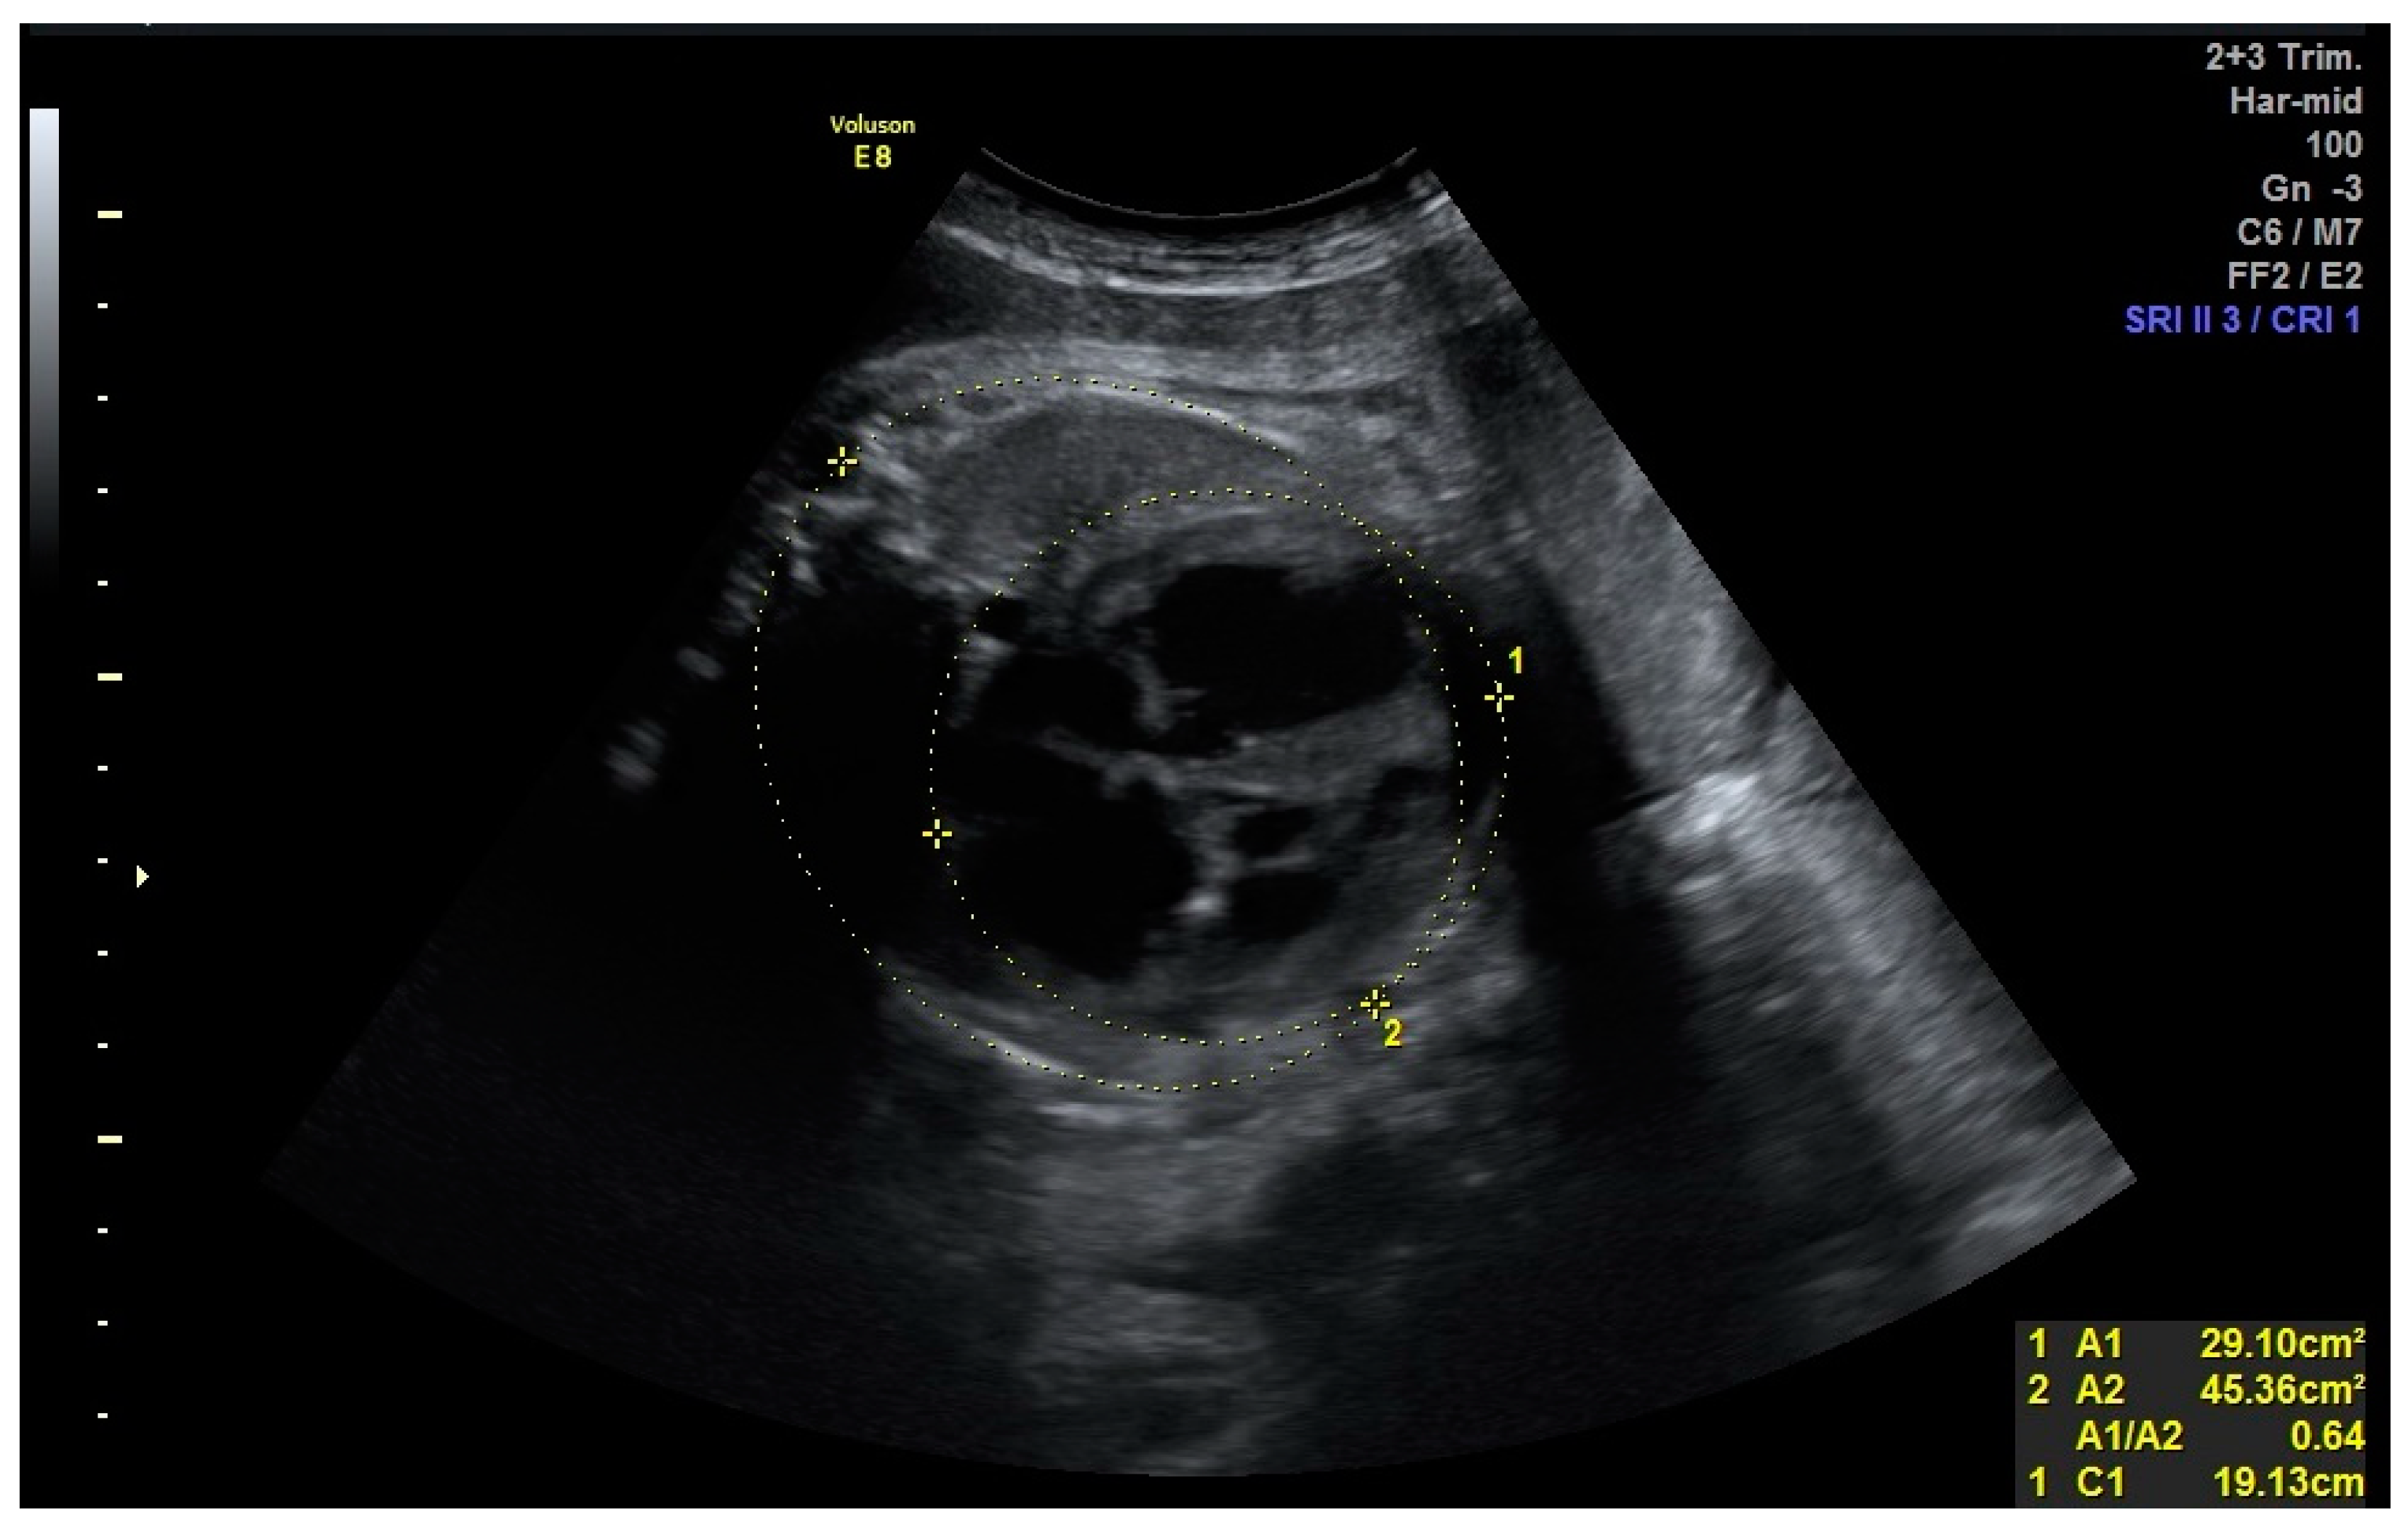

The male patient came to our attention prenatally: fetal heart pathology was first detected on the 31st gestational week when a moderate dilatation of the left ventricle along with decreased contractility was described on a prenatal echocardiogram (Figure 1).

Figure 1. Fetal cardiothoracic ratio: 31 weeks of gestation.